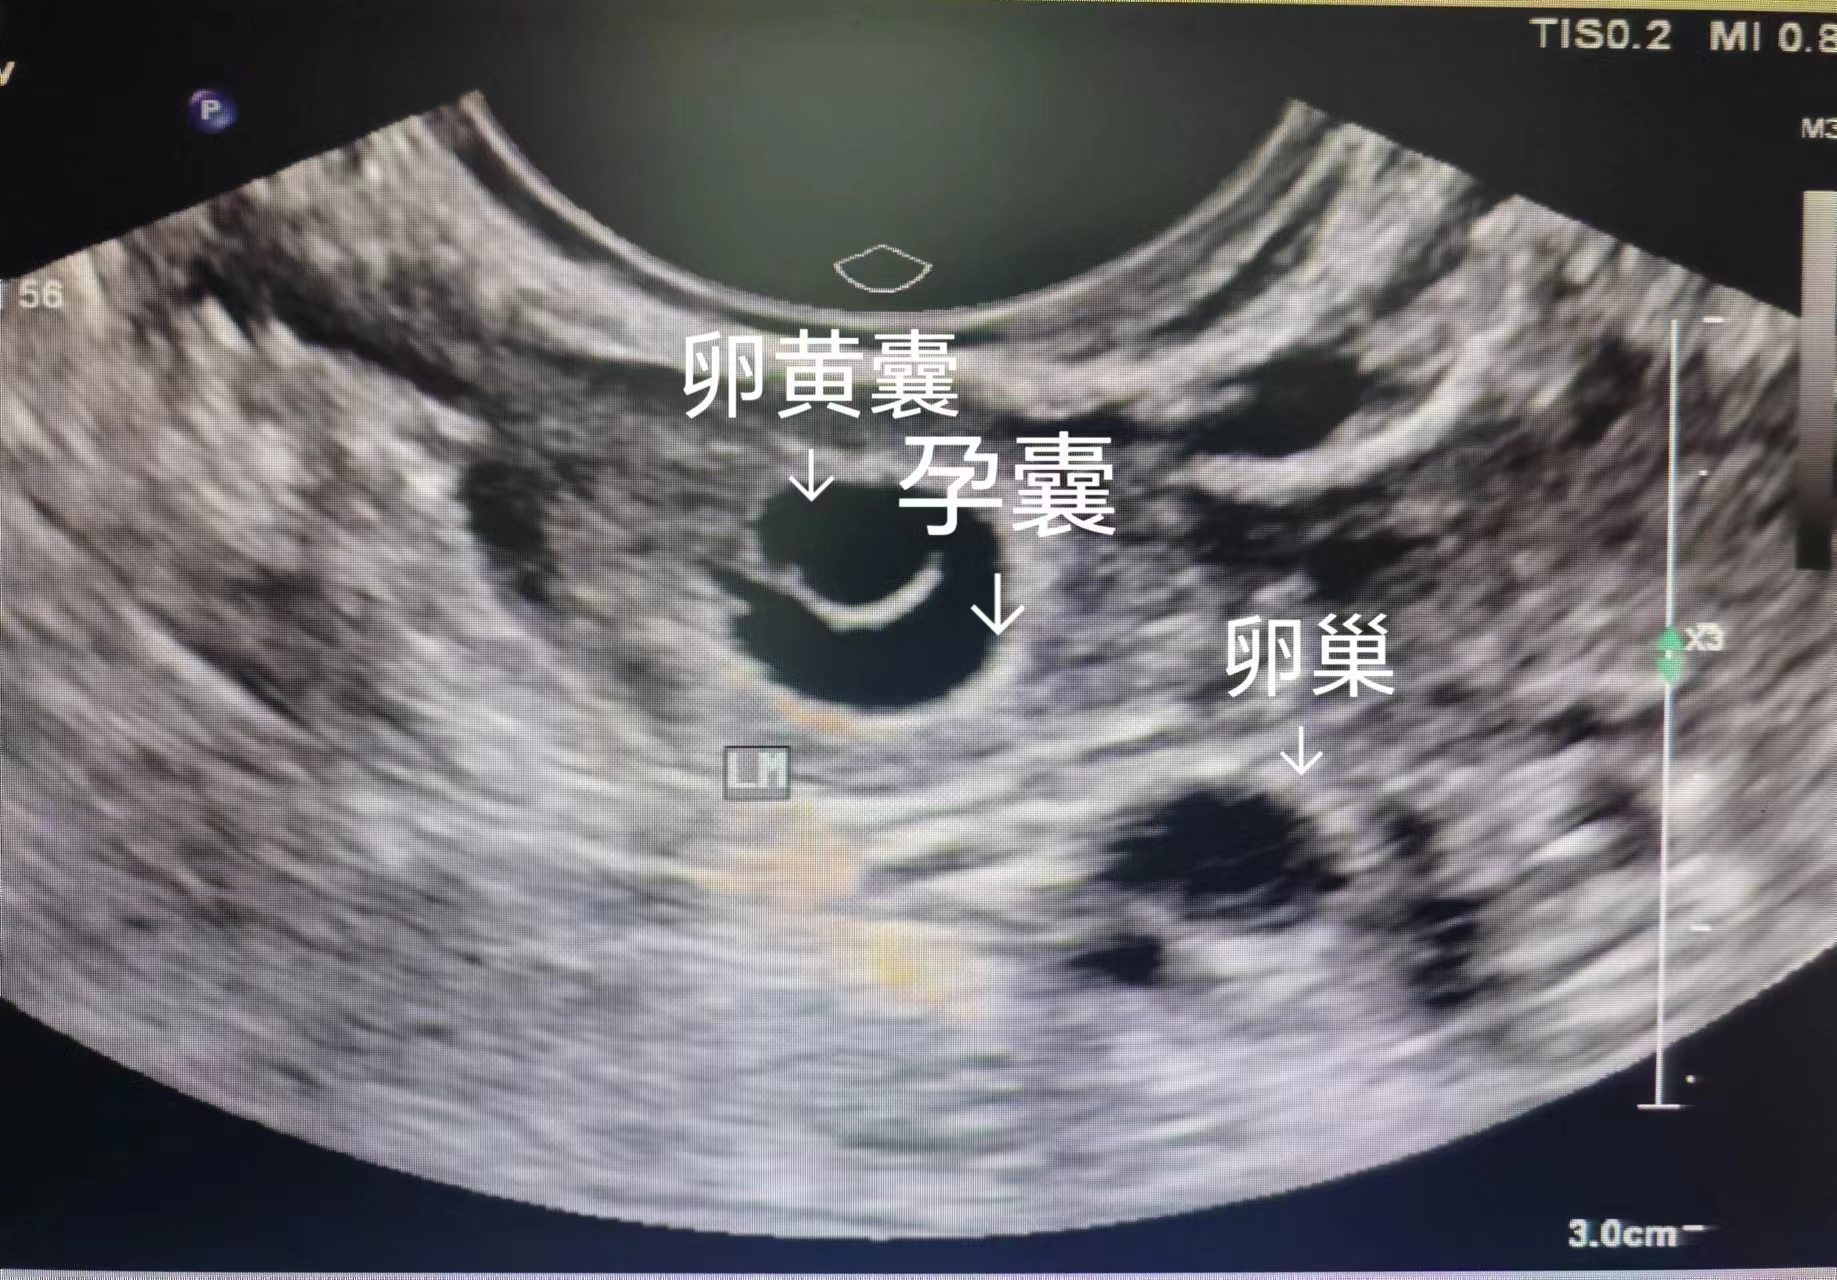

1. 精准确认“宫内妊娠”,排除致命风险

这是孕早期超声最核心的作用。通过超声可清晰看到孕囊位置,判断是否为宫内妊娠,及时排除宫外孕或葡萄胎等可能引发阴道大出血、恶变的异常妊娠)。

宫内正常妊娠